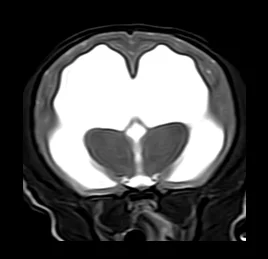

• 뇌수두증

• 후두골 이형성 증후군